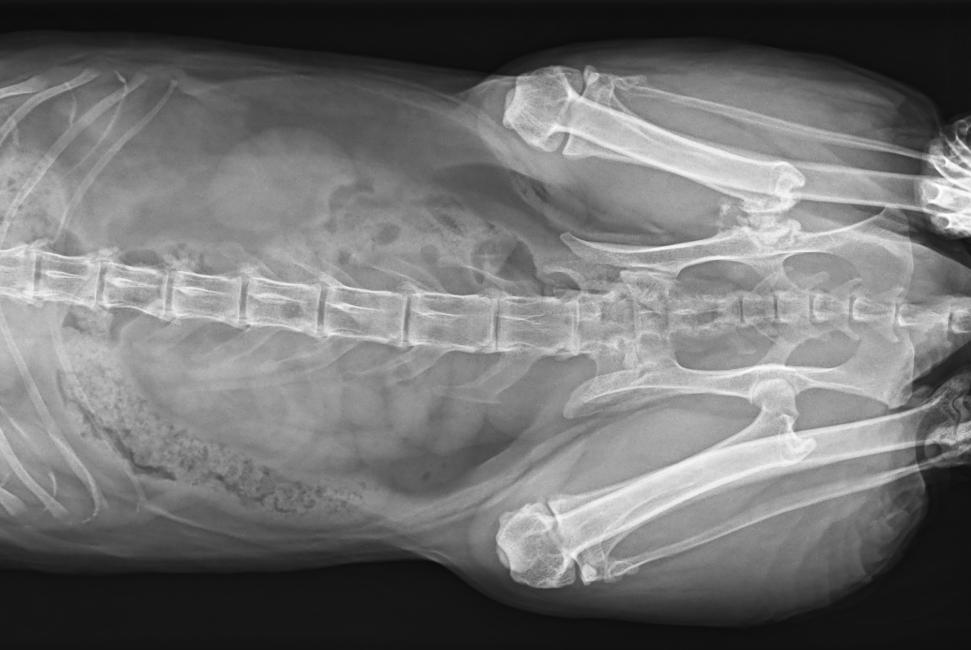

● 17*17大尺寸平板探測器,獲得高質(zhì)量圖像

● 優(yōu)異的空間分辨率及信噪比,提升圖像質(zhì)量

● 采用線(xiàn)噪聲消除技術(shù),使成像質(zhì)量提升40%

● 智能高效的圖像處理軟件,大幅提升圖像質(zhì)量